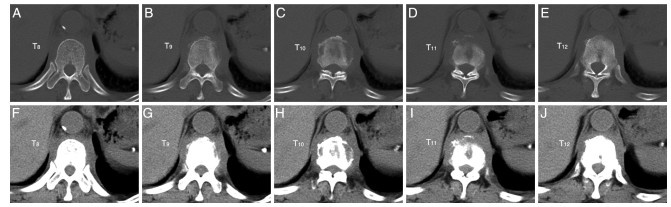

The clinical study of Bushen Huoxue Decoction combined with unilateral biportal endoscopy (UBE) in the treatment of lumbar spinal stenosis with kidney deficiency and blood stasis

E Yuan, HUANG Shengchang, RUI Lining

2025, 23(10): 1764-1767. doi: 10.16766/j.cnki.issn.1674-4152.004224

72 3

Abstract:

Objective  To evaluate the effects of Bushen Huoxue Decoction combined with unilateral biportal endoscopy (UBE) in patients with lumbar spinal stenosis (LSS) of kidney deficiency and blood stasis, focusing on recovery, inflammatory response, and postoperative complications, and to explore the therapeutic effect of integrated Chinese and Western medicine.  Methods  From June 2023 to April 2024, 120 patients with kidney deficiency and blood stasis type LSS were enrolled at Wujin Hospital of Traditional Chinese Medicine, Changzhou, and randomly divided into a treatment group (Bushen Huoxue Decoction + UBE) and a control group (UBE alone). The indicators such as visual analogue scale (VAS) score, Oswestry disability index (ODI) score, changes of serum interferon-γ (IFN-γ)/ interleukin-1α (IL-1α) were assessed.  Results  The treatment group demonstrated a higher overall response rate compared with the control group [86.67% (52/60) vs. 71.67% (43/60), χ2=4.093, P=0.043]. The VAS score in the treatment group was lower than that in the control group at 2 weeks and 1 month postoperatively (P < 0.05), while ODI score was lower at 1 and 6 months (P < 0.05). After treatment, serum IFN-γ and IL-1α levels in peripheral blood were significantly reduced in the treatment group compared with the control group (P < 0.05). The incidence of postoperative complications was also lower in the treatment group [6.67% (4/60) vs. 23.33% (14/60), χ2=6.536, P=0.011].  Conclusion  Bushen Huoxue Decoction combined with UBE can significantly improve the efficacy of kidney deficiency and blood stasis type LSS, reduce postoperative VAS and ODI scores, decrease serum IFN-γ and IL-1α levels, and reduce the risk of postoperative complications, supporting its value as an integrated therapeutic strategy.